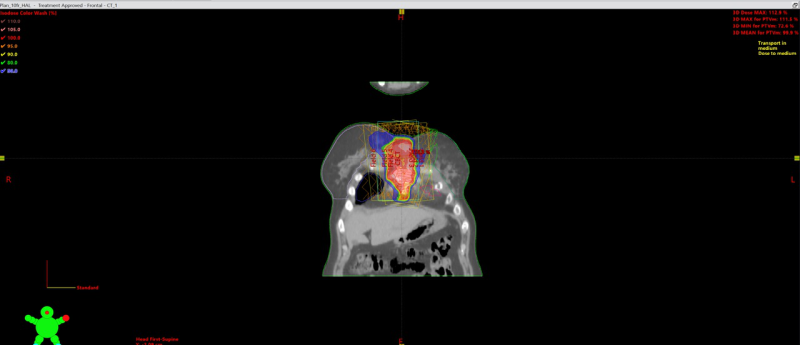

Специалистами БУЗ ВО «ВОНКОЦ» было проведено лечение метастаза рака молочной железы в грудину — сложный клинический случай, требующий высокой точности планирования и скоординированной работы специалистов.

Особую роль в успешном проведении терапии сыграла команда физико-радиологического отделения. Медицинские физики центра выполнили детальные расчёты и разработали индивидуальный план облучения на современном линейном ускорителе.

Процесс планирования включал:

– определение точного расположения лечебных полей с учётом анатомических особенностей пациента;

– выбор оптимальной энергии излучения;

– настройку углов коллиматора для максимально точного попадания в мишень;

– расчёт дозовых нагрузок для защиты жизненно важных органов и здоровых тканей.

После завершения расчётов план лечения был обсуждён и согласован между медицинским физиком и лечащим врачом-радиотерапевтом, прошёл этап верификации — проверку точности и достоверности на аппарате, на котором проводилась терапия.